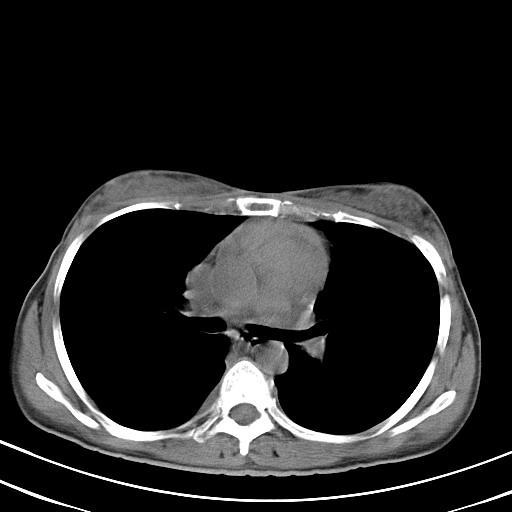

以下是引用汪涛同志在2007-8-2 0:40:00的发言:[br]病变虽然广泛,同时侵及双侧纵隔,但是无论左侧和右侧上下观察都是与右侧颈部甲状腺相延续的,而且强化幅度基本一致,又同时具有恶性病变病变的某些特征:肿块过大且密度不均,部分层面与正常纵隔结构分界不清,结合病史已有两年,考虑:胸内甲状腺肿恶变可能。[br]